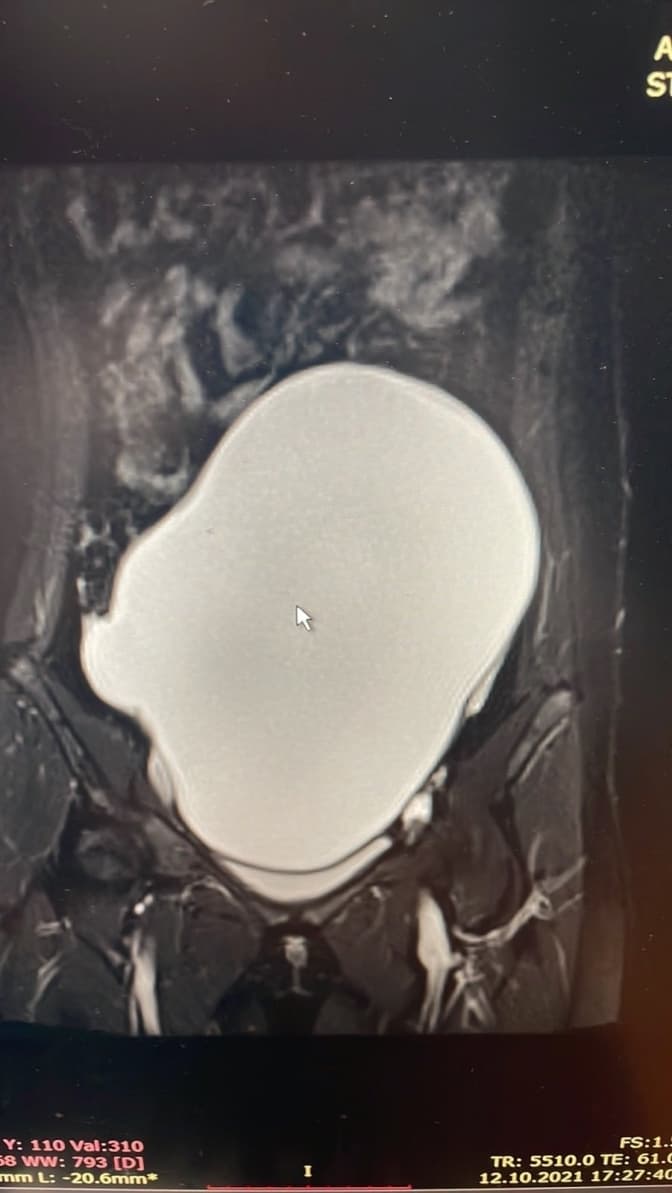

Медики львівського ОХМАТДИТу видалили величезну кісту яєчника у 14-річної дівчинки. Дитина з 9 років хворіє на лейкемію. Через лікування пухлина почала збільшуватися, та досягнула ваги 3 кг. Саме на стільки схудла дівчинка після операції, кажуть у лікарні.

Упродовж кількох років дівчинка проходить променеву і хіміотерапію. В Італії їй зробили пересадку кісткового мозку. Тепер у дитини – ремісія. У процесі лікування пацієнтка отримувала також гормональну терапію, що, імовірно, стимулювало ріст пухлини в яєчнику. Батькам дівчинки лікарі рекомендували стежити за кістою, але згодом вона виросла до величезного розміру. Жодних симптомів не було, в дитини лише збільшився живіт.

Лікарі ОХМАТДИТУ видаляли пухлину малоінвазивним методом, тобто через маленькі проколи, а не розріз через увесь живіт. У результаті отримали близько 3 літрів рідини та масивну капсулу пухлини.

«Ситуація була непростою, адже гігантське утворення в яєчнику було бомбою і вже навіть не сповільненої дії. Компресія навколишніх органів і ймовірність злоякісної трансформації самої пухлини вимагали швидкого реагування ! Усе заплановане в операційній нам вдалося. Попереду у дівчинки ще тривалий процес реабілітації репродуктивної функції», – каже дитяча гінекологиня Еліна Чайківська.

Фото ОХМАТДИТу